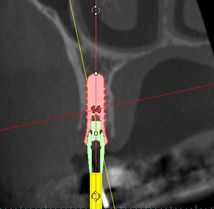

Aufgrund der detailgetreuen dreidimensionalen Darstellung von Zähnen und Kieferknochen und durch die geringe Strahlenbelastung steht die 3D Volumentomographie für eine Vielzahl von Indikationsbereichen zur Verfügung, wie zur räumlichen Diagnostik von Wurzelkanälen und parodontalen Strukturen, zur Beurteilung von Nachbarstrukturen, wie Zähne, Implantate, Kieferhöhle und Nerven, zueinander. Dadurch läßt sich eine verbesserte Diagnose- und Planungssicherheit erreichen.

In der Implantologie kann mit Hilfe der exakten 3D Diagnostik das vorhandene Knochenangebot genau auf Qualität und Quantität untersucht werden, wodurch eine optimale Nutzung des Knochens möglich wird. Auch lassen sich sensible anatomische Strukturen, wie Nerven oder Kieferhöhle genau erfassen, wodurch in Verbindung mit dreidimensionaler Planung die Sicherheit für den Patienten erhöht wird.